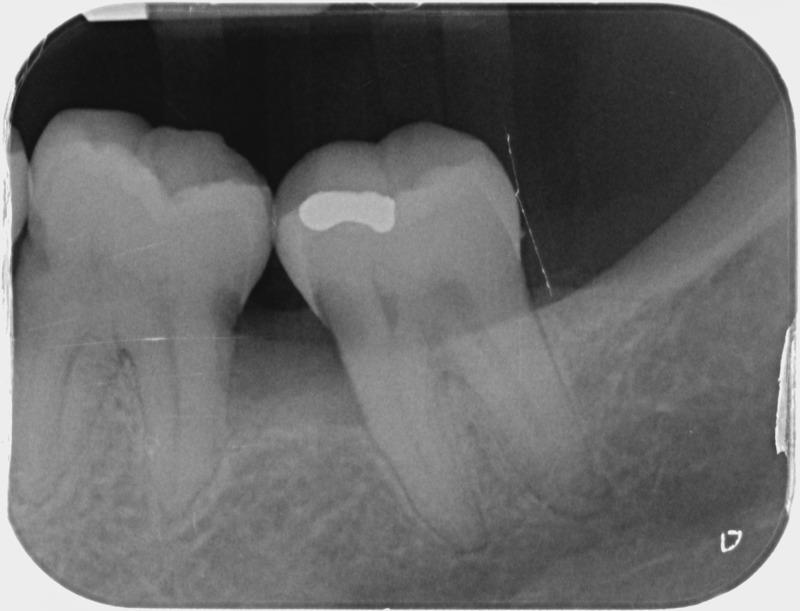

Avant

• Traitement endodontique : Sous anesthésie locale et à travers la protection d’un champ opératoire nous accédons à la pulpe de la dent à soigner, puis aux canaux de ses racines que nous devons désinfecter. Ce soin nécessite l’élimination complète de la source de contamination (souvent la carie) parfois sous une ancienne reconstitution ou une couronne qu’il faut alors retirer. Une fois le nettoyage et la mise en forme des canaux réalisés, nous les obturons de façon hermétique avec un ciment et un matériau thermoplastique appelé Gutta Percha. Ceci afin d’empêcher une nouvelle prolifération bactérienne et d’assurer le maintien de la dent dans ses structures de soutien (ligament parodontal et os alvéolaire). L’ouverture effectuée au centre de la dent sera d’abord refermée avec un pansement provisoire avant d’envisager ensemble la reconstitution d’usage : un composite, un inlay-onlay ou une couronne.